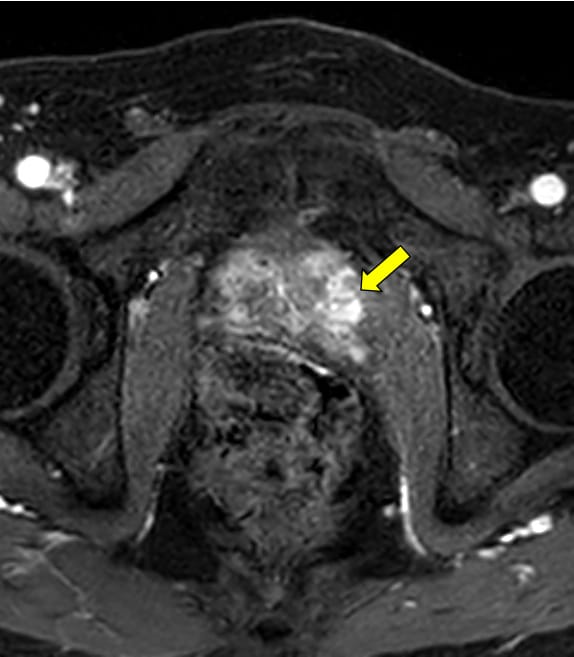

本症例ではPSA高値を契機に前立腺MRI検査を施行した。便秘症があるため、直腸は拡張し、内部にガスを含む便塊を認める。鎮痙薬は、既往症のため、使用せず、検査前の排便も不可能であったために、画質劣化が避けられない。腸管ガスによるひずみの影響で、全ての撮像シーケンスで、前立腺の後方の辺縁は不鮮明で、内部の信号が不均一となる。特に空気や蠕動の影響を受けやすい、拡散強調画像での画質劣化が著しい。

拡散強調画像(DWI)では、腸管ガスによるひずみの影響を減らすため、echo planar imaging(EPI)を用いたDWIよりTurbo spin echo(TSE)を用いたDWIを使用する。high b valueの画像は、computed DWIで作成することで、実際の撮像よりもノイズを低減できる場合がある。また、ダイナミック造影MRIを追加すると、短時間撮影のため前立腺の輪郭も明瞭で、癌部と非癌部のコントラストがつき、病変の検出に役立つ場合がある。